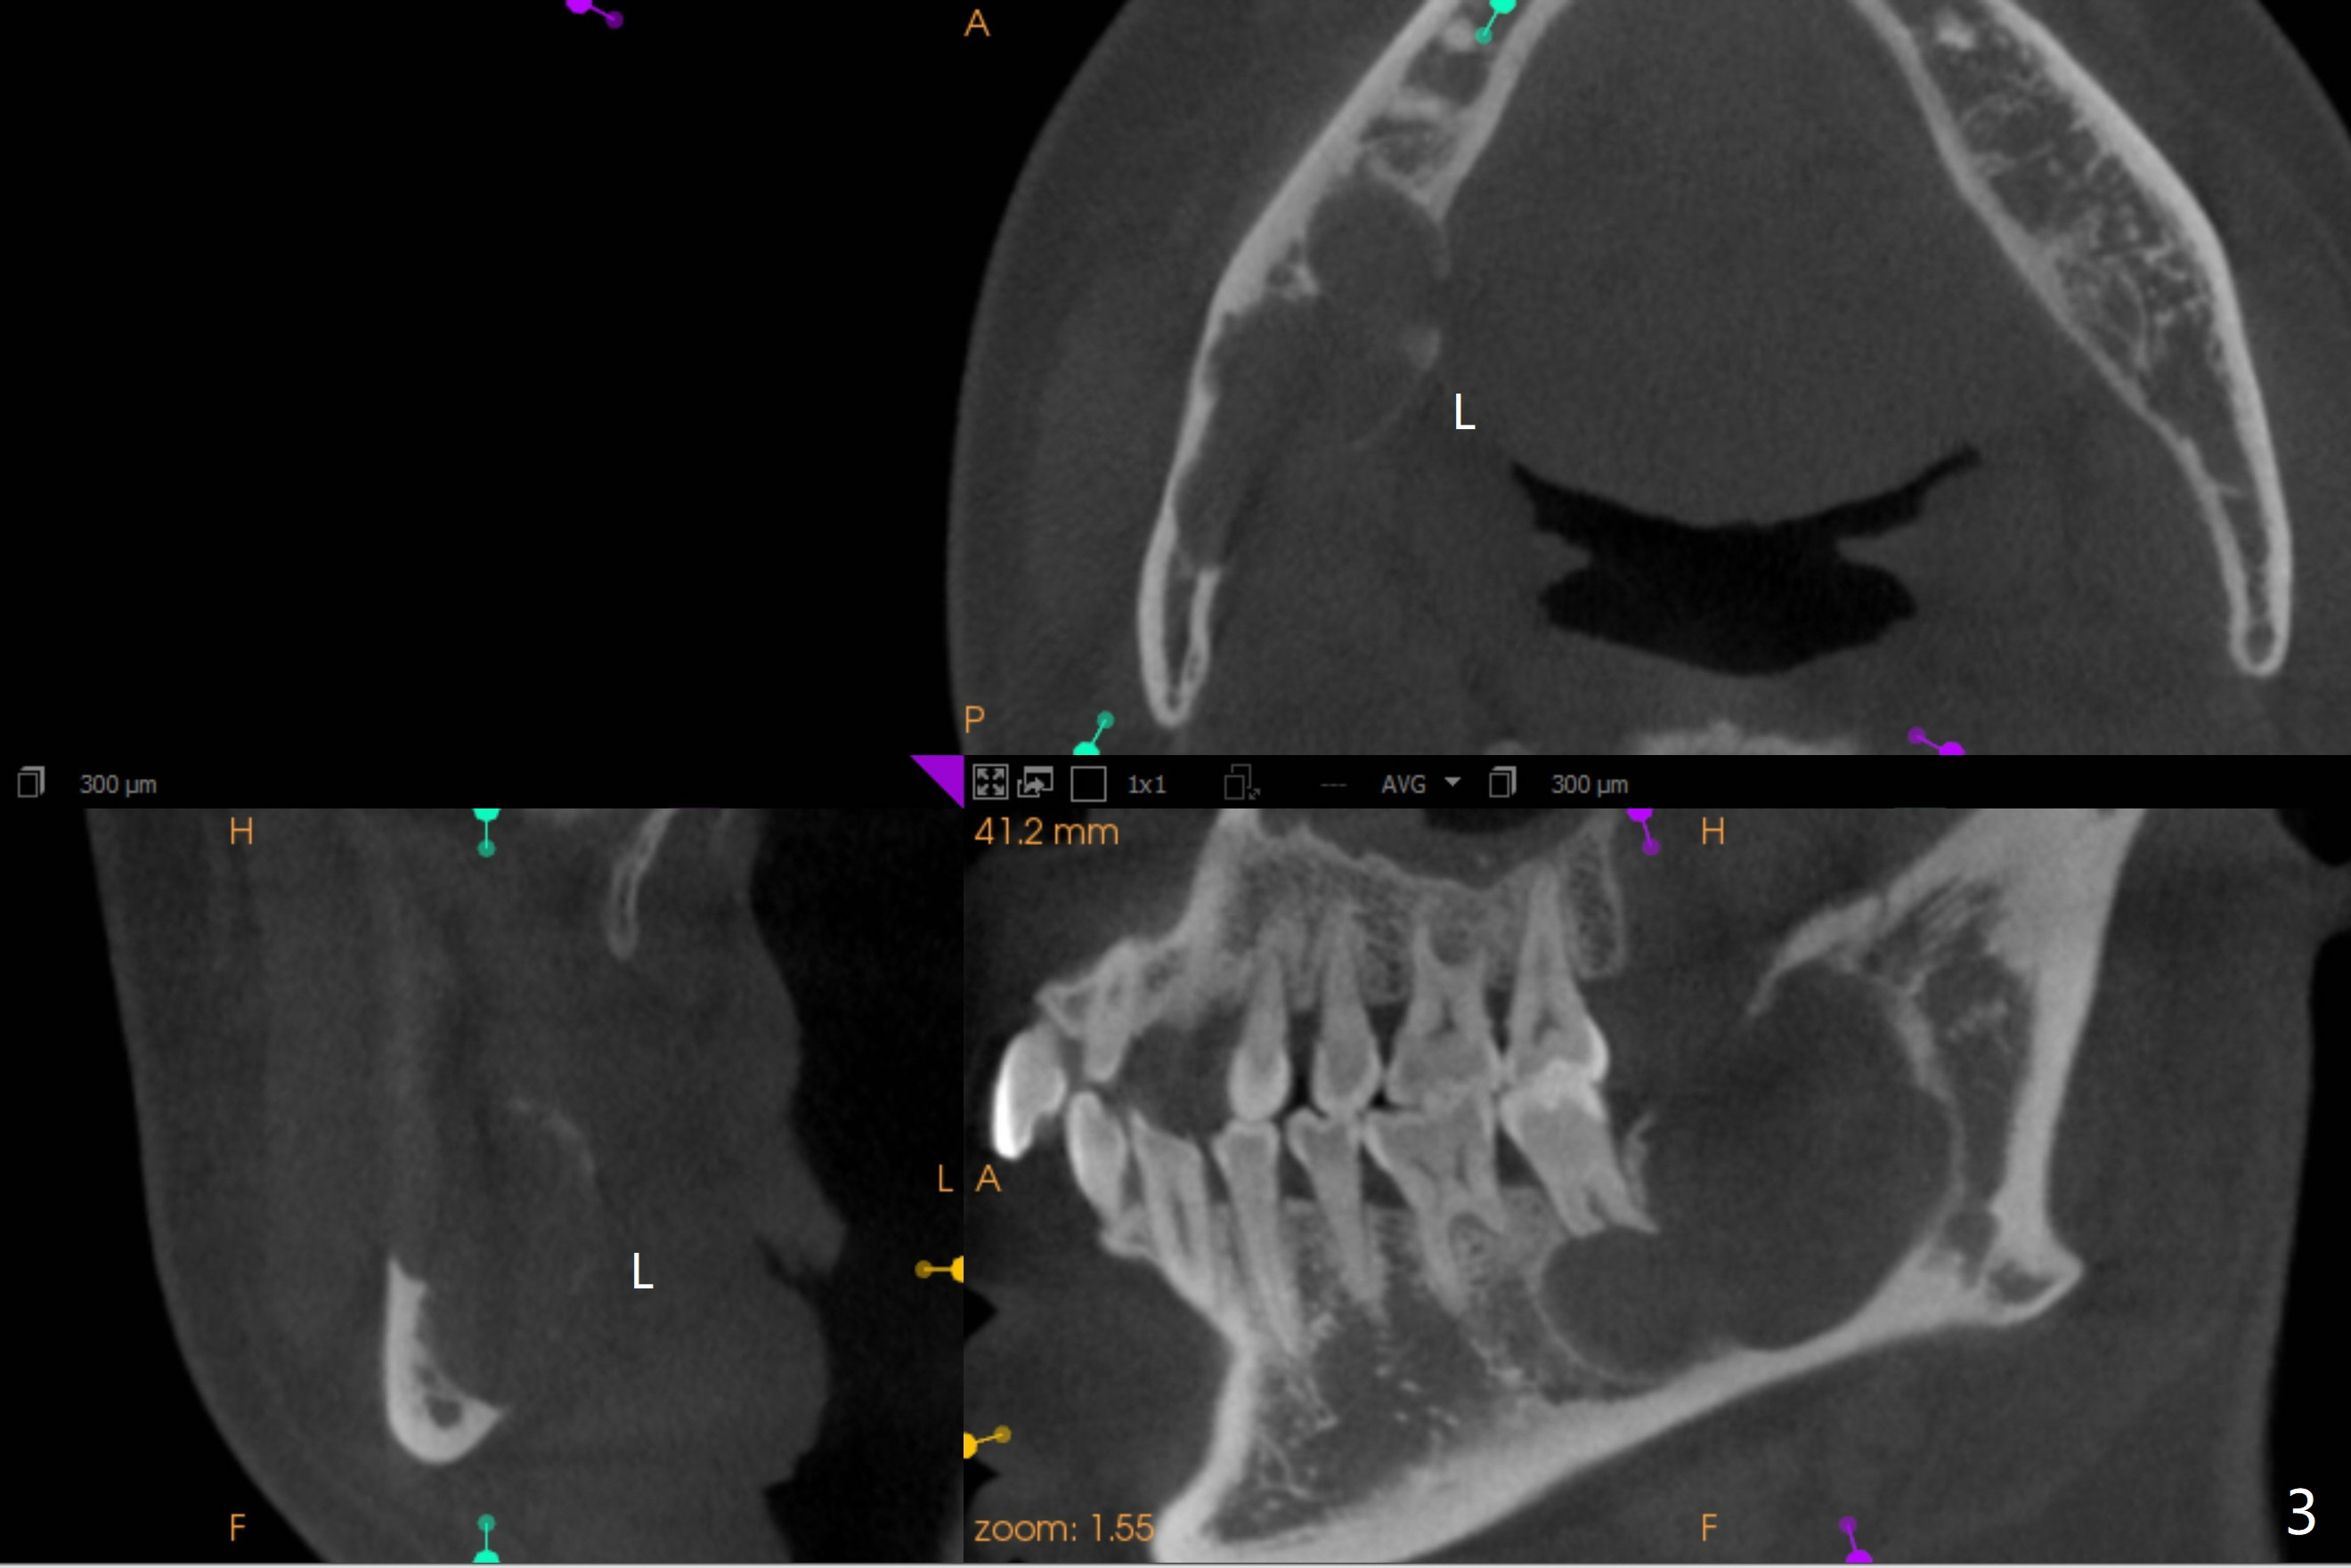

术前CT显示舌侧骨板吸收(图三)。术后全景片显示三个磨牙拔除,髂骨植骨,钢板固定(图四)。

神经应被压迫在颌骨下缘  这X线片上看不到  要看断层  这病例陈平兄是专家

我在日本大学口外20年 清楚他们的治疗方法  这病例还有舌侧骨壁吸收?  向升枝上方浸润(?)  边界不清  也是造釉细胞瘤的特征  记得国内  以前为彻底根治  防止复发 选择截骨方法  在日本  看到相似病例  选择保留颌骨的治疗  看这病例  虽骨吸收区大  但仍有相当骨组织存在 做术中快速切片确诊  切开翻瓣  彻底刮扒干净后 用大圆钻头  尽可能磨除肿瘤区浅层骨面  如需要  用金属板在颊侧下缘固定防骨折(这病例好像不需要)  置皮片引流  缝合关闭  争取I期愈合  关键是术后隔3月  6月  X线复查  如有骨吸收复发  再次做局部手术去除肿瘤组织  这样不截骨  成功可能性较大  当然  最后不能控制  还是要截骨  定期复查是关键  期待听到口外专家的高见[Trick][Trick]